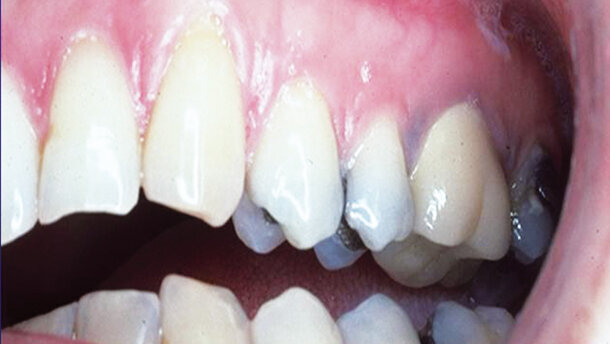

Fig. 3: Before—showing UL cuspid (#10) with root exposed accentuating the visual contrasting difference between the adjacent lateral and first bicuspid teeth.

Figs. 1–4: Before treatment. Showing labial recession of the UR cuspid. The root exposed showing enamel with no sensitivity. The isolated recession stands out as an unaesthetic eyesore (Fig. 1). Final view showing regeneration of healthy gingival mucosa with regeneration attaching it to the root aesthetically. It blends with the adjacent teeth. Its maintainable, and the healthy, pinkish white keratinized tissue is now attached, allowing the maintenance of the aesthetically pleasing result (Fig. 2). Before—showing UL cuspid (#10) with root exposed accentuating the visual contrasting difference between the adjacent lateral and first bicuspid teeth (Fig. 3). Diagramatically the arrow points to the recession of #11. The horizontal dotted line shows the difference between #11 and the lateral. Also allows visualization between it and the bicuspid (Fig. 4).

Case II presents an example of a patient who has tooth with recession, exposing the root, and affecting the adjacent tooth aesthetically, as well. This example is much more commonly seen, but is often overlooked because it lacks the sharp contrast seen in Case I. This sophisticated diagnosis was referred to my office by a local general dentist because the recession in this type of case caused the appearance of a much longer tooth, compared with the adjacent tooth (in this case the lateral). The recession emphasized the apical length of the cuspid, especially in relation to the lateral. The curved incisal edge of the lateral was completely overlooked, especially in comparison with the recession. Also the apical recession of the cuspid stood out in contrast to the distal bicuspid.